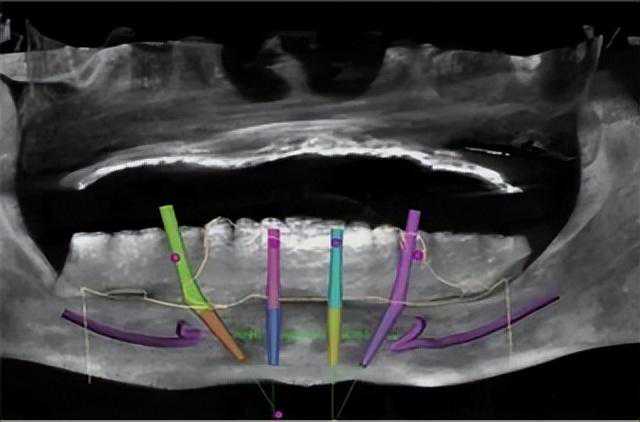

手术前,医生先给周先生做了一套详细的身体检查,并进行了口腔扫描CBCT数据分析,发现他除了血脂有点高,身体还算健康,外加上缺牙时间不算太长,牙槽骨萎缩程度较轻,于是为他选择了ALL-ON-4全数字化种植技术,先进行下颌牙的种植修复。

导入CT数据后,在电脑上设计ALL-ON-4种植方案

All-ON-4是一种基于CBCT+3D+种植导板技术,最大特点是在需要种植的上颌或下颌植入4颗种植体,然后在种植体的基台上安装半口拱形牙冠,从而实现即刻种植即刻戴牙。

手术开始后,医生根据周先生口腔的数字模型,用黑格3D打印机打印出了专属于他的定制化种植导板,不仅完全贴合牙龈,还能辅助植体精准植入,避免偏钻、钻穿等意外。